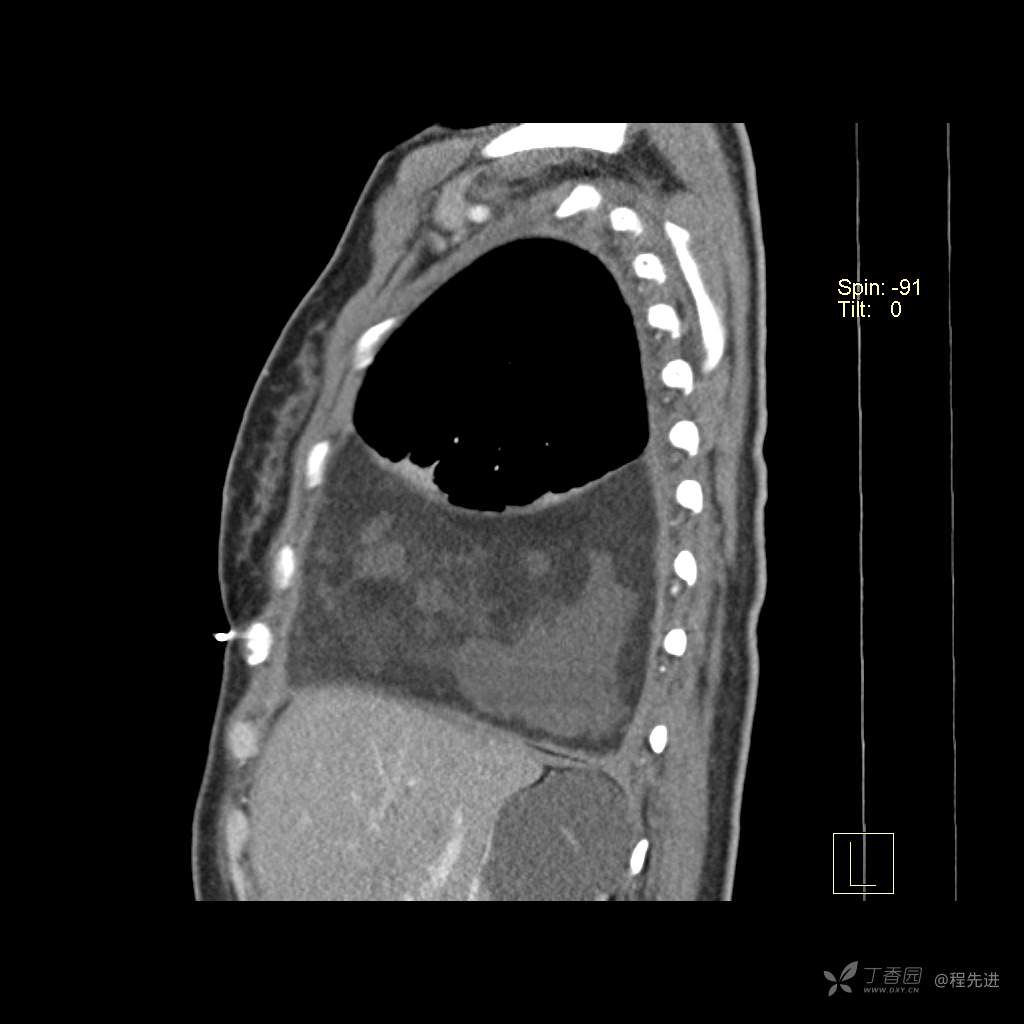

患者性别:女

患者年龄:51岁

简要病史:胸闷半年

肺淋巴管肌瘤病 (7)

乳糜胸 (8)